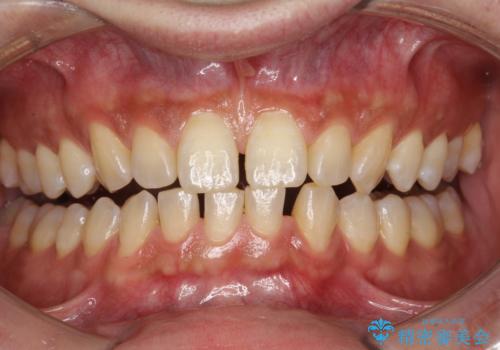

- ホワイトニングで、できる限り白くしたいとのことで来院されました。処置前クリーニング(¥3,300)・エクセレントホワイトニング(¥29,700)・トリートメント(¥550)を行いました。